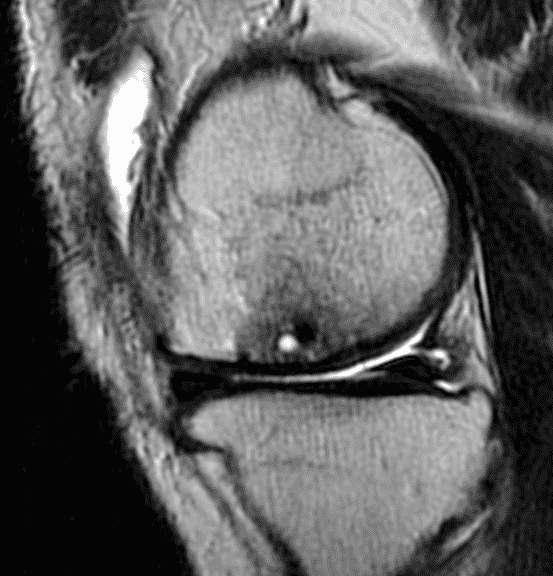

A 32-year-old man suffered a traumatic chondral injury to the medial femoral condyle that was treated with an osteochondral allograft 20 months previously. Representative images from a current knee MRI include (1A) coronal fat-suppressed fluid-sensitive and sagittal (1B) T1-weighted, (1C) proton density-weighted, and (1D) T2-weighted sequences. Are the post-operative MRI findings normal and expected, or abnormal and pathologic? Based on these images, would you characterize the procedure as a success or failure?

Figure 2: (2A) On the coronal image, the margins of the osteochondral graft are faintly visible (arrowheads). Both the graft and underlying bone show mild marrow edema, an expected finding. (2B) The T1-weighted image shows continuity of the marrow in the graft (asterisks) with the underlying bone, indicating osseous integration. A bioabsorbable pin (arrow) used for graft fixation is partly visible. (2C) The proton density-weighted image shows a low signal intensity seam (black arrow) between the native cartilage and transplant, as well as a defect in the subchondral bone plate of the graft (red arrow) where the pin was drilled, both normal findings. (2D) The T2-weighted image shows a smooth, congruent articular surface (arrows), restoring the normal anatomy, and a tiny subchondral cyst. No findings are present to suggest graft failure. The patient’s current symptoms were attributed to pathology elsewhere in the joint (not shown).

Successful osteochondral allograft procedure.